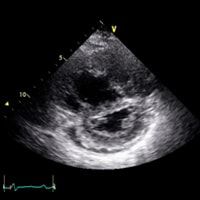

Echocardiogram

If your doctor suspects you have PH based on your history, risk factors, and physical examination, he or she may order an echocardiogram. In this non-invasive procedure, electrodes are placed on your chest to monitor your heartbeat, and sound waves are used to create a moving picture of your heart. When performing an echocardiogram, your doctor will look for:

While an echocardiogram alone cannot diagnose CTEPH, it can determine if you have some type of PH. If the results of your echocardiogram suggest you may have PH, your doctor will perform additional tests to find out more.

Images courtesy of Dr. Nick Kim, University of California, San Diego.